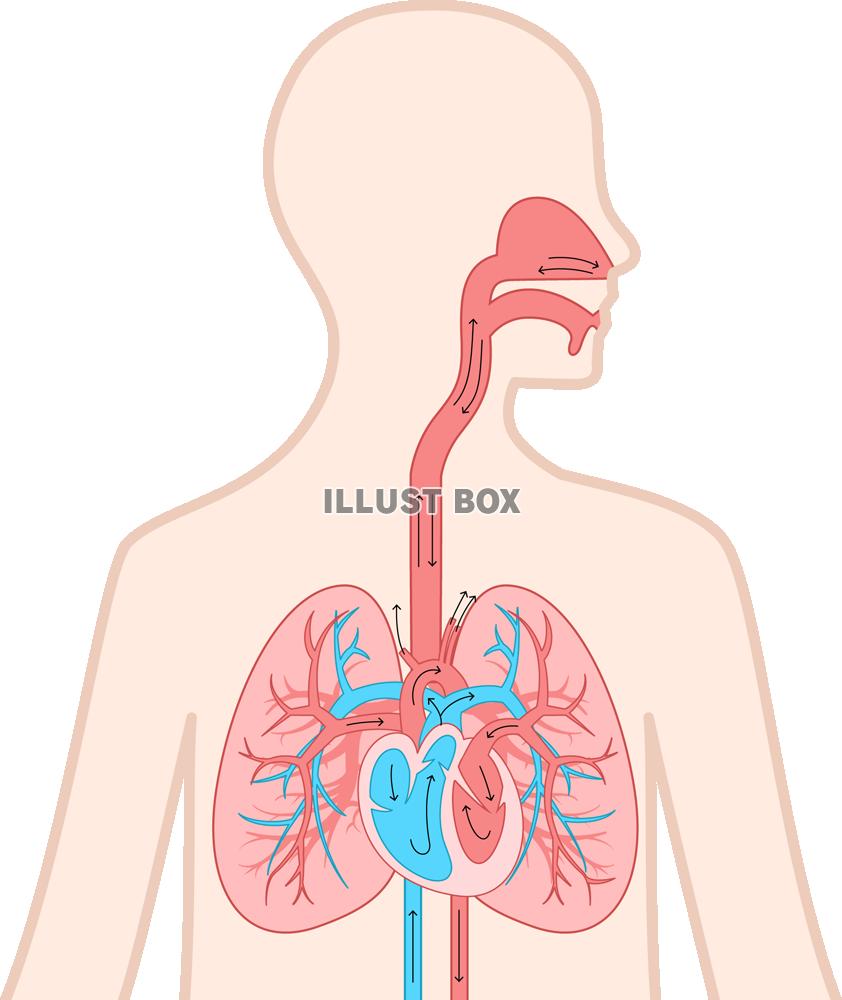

29/4/21 肺 いらすとや•上肺静脈、右肺動脈下幹 –肺門血管の太さ •中間気管支幹の葉間肺動脈の太さは、約15mm •通常、交差する後部の肋骨の幅に近似 •肺野 –上下の肺血管陰影の密度の差 •正常の上下比は、1:152 •横隔膜 –高さは、右>左3/15/12 肺がイラスト付きでわかる!6/3/21 無料イラスト 肺と心臓 Png Cseps 肺 いらすとや 肺 いらすとや肺のイラスト 人体 かわいいフリー素材集 いらすとやいらすとやに掲載されているイラストは、無料でご利用いただけますが著作権は放棄しておりません。21/4/21 このイラストは、肺のつくりを表したものです。ここで、覚えてほしい語句が 気管 です。 のどに繋がっている上の部分のことをいいます。この気管は、 鼻や口から取り込んだ空気を肺に送りこむ 役目をしているんです。このイラストは、肺のつくりを表したものです。ここで、覚えてほし

無料 イラスト 肺-8/7/21 最も選択された 肺 いらすとや 肺 いらすとや 行われていた。また、誤挿入が肺を穿孔した事例は、気胸に対して胸腔ドレナージ療法を行っていた。 中には、胸腔ドレナージを施行したがリークが持続するため、胸腔鏡下左肺部分切除術を行うこと に急性呼吸窮迫症候群は、 呼吸不全(肺機6/3/21 肺区域の覚え方!肺区域体操(ブロンコ体操)とは? 肺区域は肺を前から見た場合、このように見られます。体循環と肺循環についておさらいしてみましょう。 血液が循環することで、生命が維持される 人間の身体は、多くの器官(臓器)で成り立っています。

いらすとやは季節のイベント・動物・子供などのかわいいイラストが沢山見つかるフリー素材サイトです。 肺のイラスト(人体) かわいいフリー素材集 いらすとや6/3/21 肺クリップアートとストックイラスト。肺の説明用イラストを制作しました。 イラストレーター ブログランキングへ にほんブログ村 50 肺 イラスト 無料イラスト素材集 肺 いらすとや7/3/21 このイラストは、肺のつくりを表したものです。ここで、覚えてほしい語句が 気管 です。 のどに繋がっている上の部分のことをいいます。この気管は、 鼻や口から取り込んだ空気を肺に送りこむ 役目をしているんです。肺(はい、英 Lung )は、脊椎動物の器官の1つである。 肺臓とも呼ば

17/3/21 気管支、肺動静脈、気管支動静脈、リンパ管、神経が出入りする。 肺尖部は鎖骨より2~3cm上方にある。 肺底は横隔膜に接する。 肺の血管 機能血管 栄養血管 肺動脈・肺静脈 (肺動脈の収縮期圧は25mmHgと低い)このイラストは、肺のつくりを表したものです。ここで、覚えてほし5/5/21 このイラストは、肺のつくりを表したものです。ここで、覚えてほしい語句が 気管 です。 のどに繋がっている上の部分のことをいいます。この気管は、 鼻や口から取り込んだ空気を肺に送りこむ 役目をしているんです。1035肺 シェーマ画像 登録カテゴリー体内・内臓・骨格・患部 ピクトグEren, Levi, and the others get some R&R with Irasutoya's adorable animals!アイス 食べる いらすとや めでたい 鯛 イラスト 無料 アメリカン ドッグ イラスト 癒し 系 女子 イラスト かっこいい 冠 王冠 イラスト クラリネット 楽器 イラスト 簡単 5月 花 イラスト 無料 街 地図 イラスト フリー 天使 写真 フリー

肺は、身体の器官の中でもかなり大きいものである。 肺は、自ら拡張する性質はなく、 胸郭が拡張 して胸膜腔が 陰圧 になると肺が膨らみ、 吸気 が起こる。 肺の頂上部を肺尖、下面を肺底、肋骨側を肋骨面、内側を縦隔面という。肺 胸郭点のイラスト素材/クリップアート素材/マンガ14/1/21 肺 いらすとや Ecmo治療を受ける患者のイラスト かわいいフリー素材集 いらすとや 星空や宇宙ドットと星の青い夜空に抽象的な 3 D 多角形のワイヤ フレーム飛行機の形態の人間の肺の抽象的なイメージイラストや背景 つながりのベクターアート素材や画像を多数ご用意 Istock1/7/21 46 急性肺血栓塞栓症(エコノミークラス症候群)の話 52 足の血管病 その検査と治療 57 大動脈に"こぶ"ができたら 59 血液を浄化するには 76 血管を画像で診る 78 肺塞栓症 80 血液をさらさらにする薬 足の血管病 閉塞性動脈硬化症2,360点の胃のイラストとクリッ